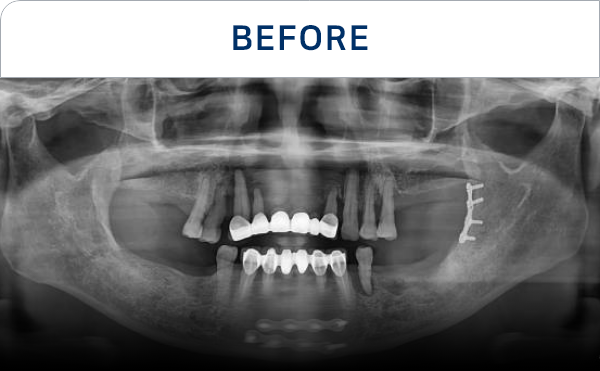

구강 상태와 필요한 치료를

정확하게 파악합니다.

CT·스캔 등 디지털 장비로

촬영 후 정밀 분석을 진행합니다.

뼈 상태·신경 위치 등을 고려해

식립 위치와 시술 계획을 세웁니다.